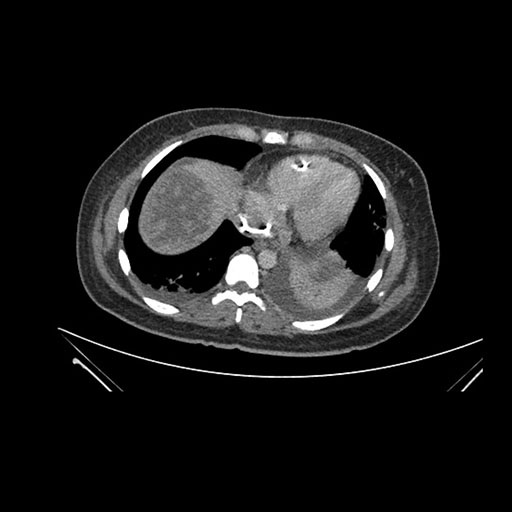

Axial Venous

Imaging analysis

Based on initial findings, which issue(s) would you be most concerned about?